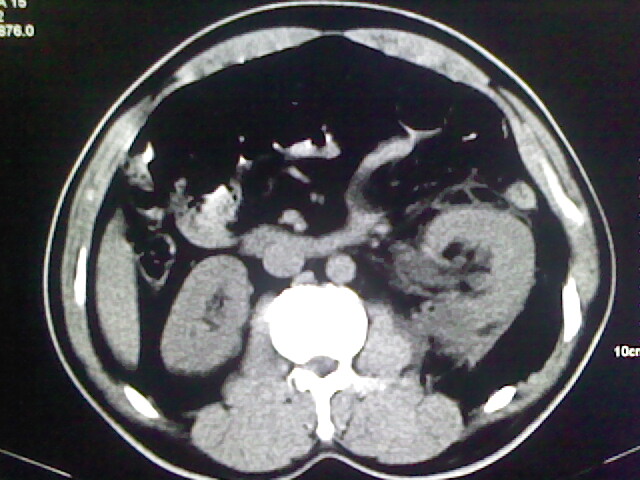

以下是引用zsl6918在2009-2-7 7:29:00的发言:[br]请提供介入的方式方法,肾及输尿管改变考虑与介入损伤有关,漏了,尿液外渗。

以下是引用余辉在2009-2-7 8:27:00的发言:[br]可能是硬化剂烧穿囊壁进入肾盂输尿管了,尿漏。不除外介入或碎石术后合并感染[br]患者术后怀疑结石,接着就碎石了?就怀疑没有确诊吗?碎石用的什么方法?气压弹道还是体外超声?如果这样的话责任人都难找

以下是引用随光逐影在2009-2-7 8:46:00的发言:[br]支持3楼意见。[br]另:不排除左肾及肾周感染可能。